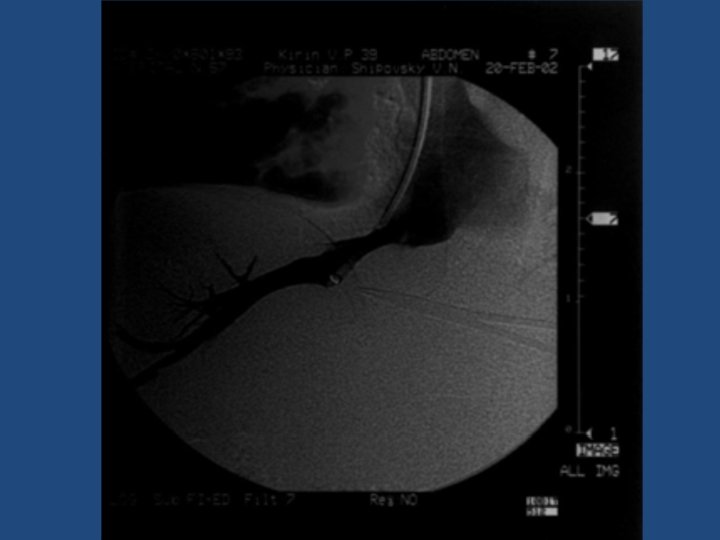

Результаты TIPS • • • Длительность процедуры 1 час до 3, 5 часов Повторные кровотечения – 10% Стеноз стента в течение двух лет – 20% Печеночная энцефалопатия Летальность 20% Максимальный срок наблюдения = 5 лет

Методика дистанционного обследования после TIPS • Клинический осмотр и лабораторные анализы • ЭГДС • Ультразвуковое дуплексное исследование портального кровотока • Ангиография ?